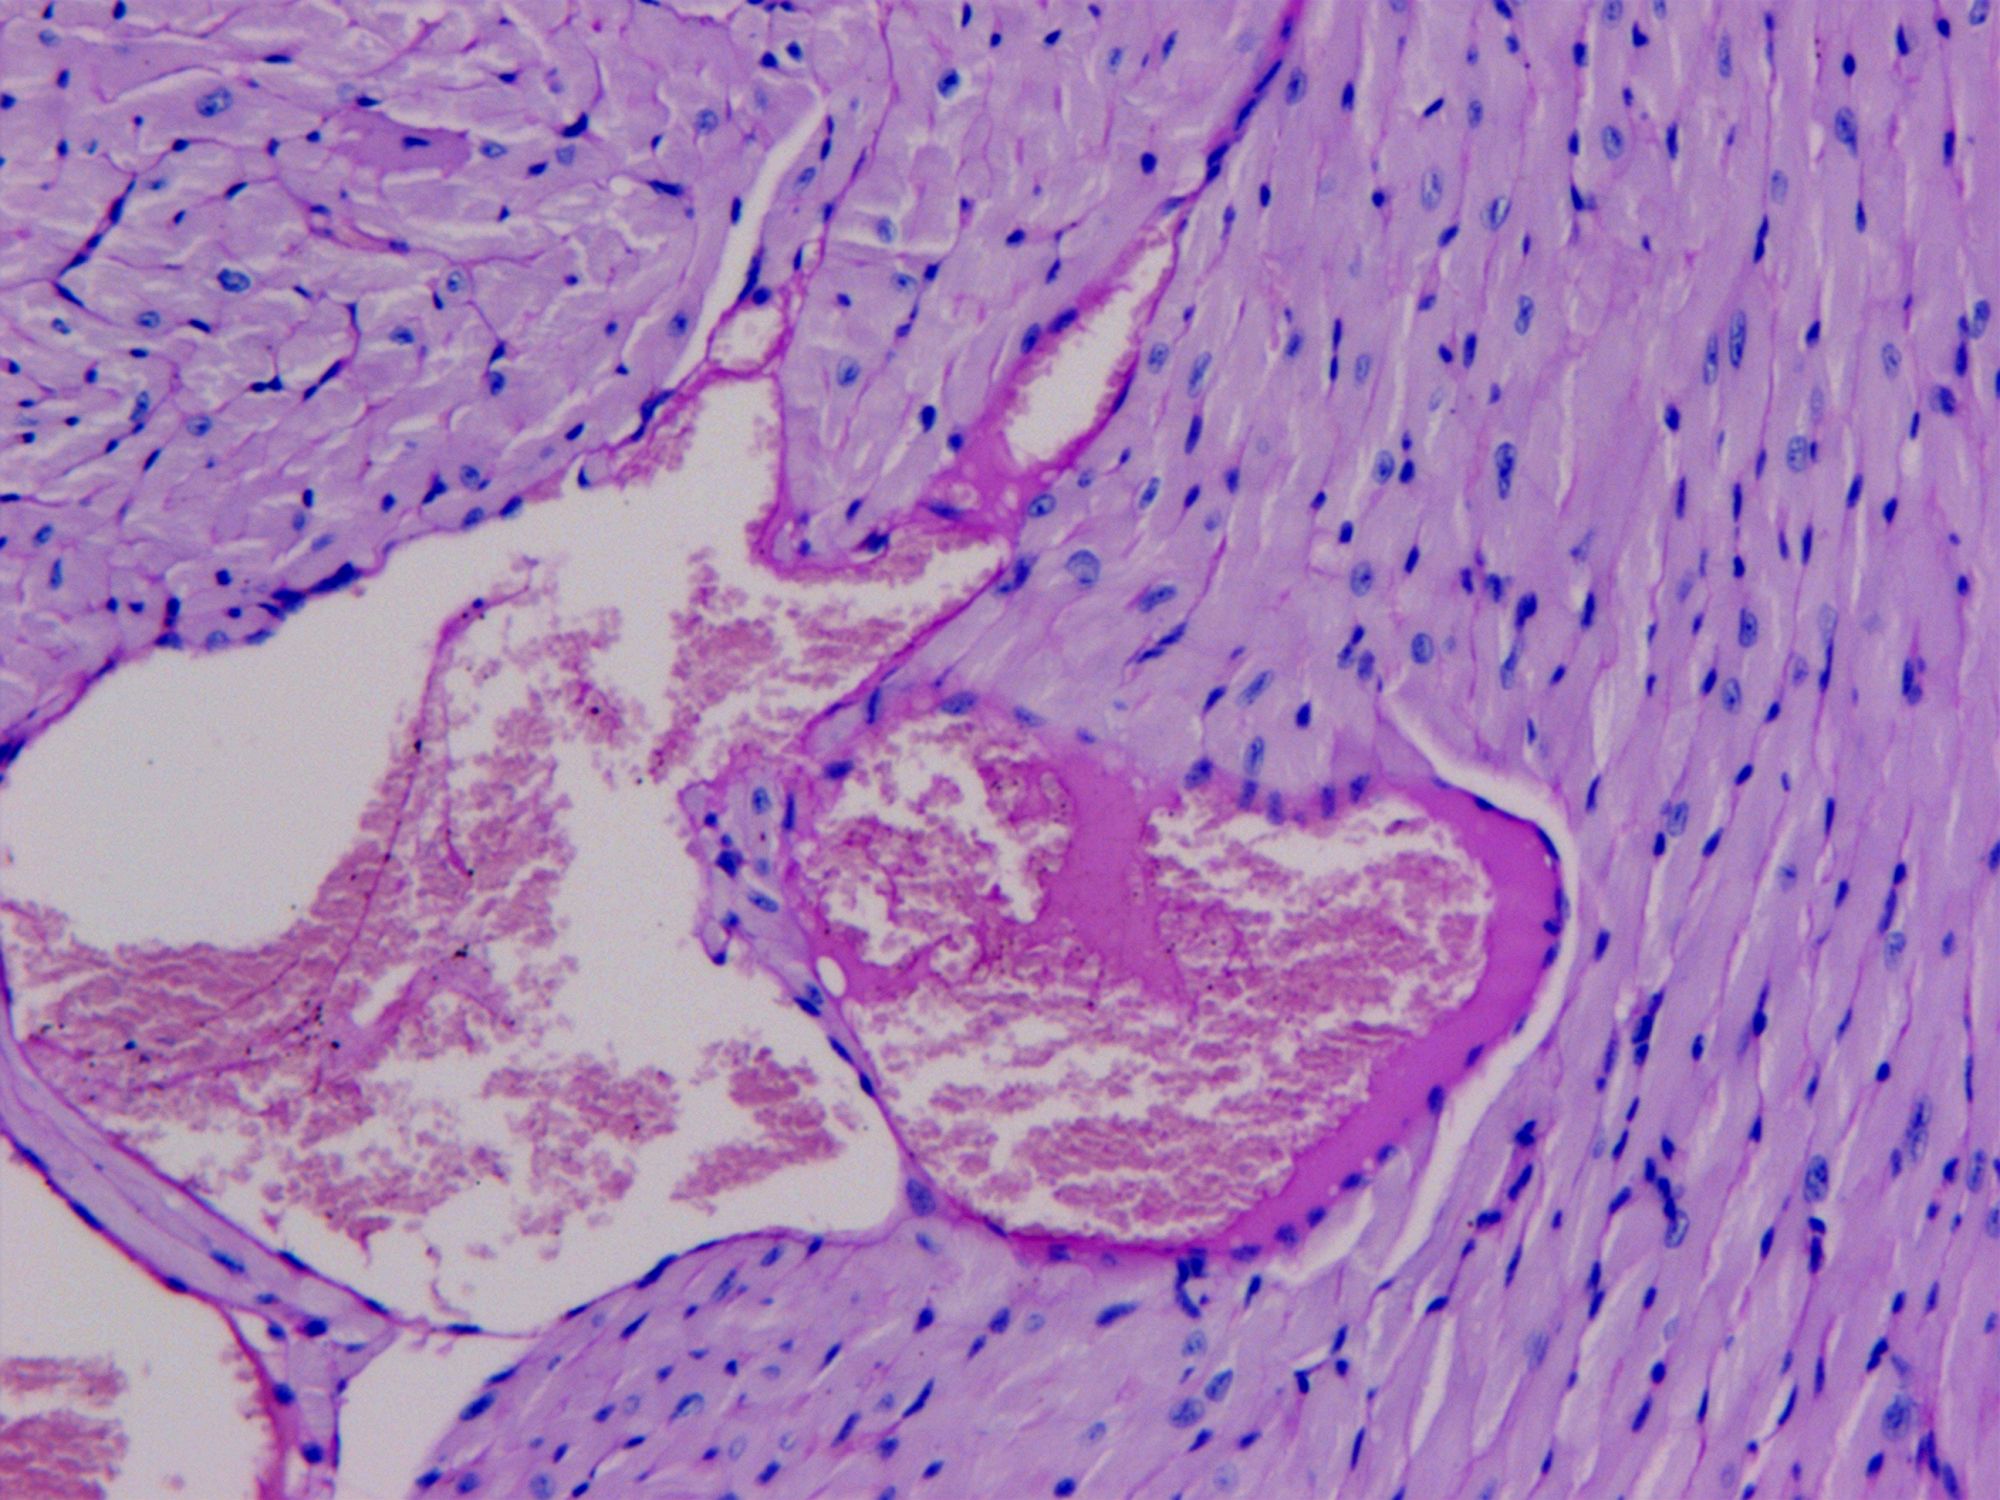

PAS糖原染色

PAS染色法(Periodic Acid-Schiff stain)在組織學(xué)上,又稱過(guò)碘酸雪夫染色,糖原染色。一般用來(lái)顯示糖元和其它多糖物質(zhì),過(guò)碘酸把糖類相鄰兩個(gè)碳上的羥基氧化成醛基,再用Schiff試劑和醛基反應(yīng)使呈現(xiàn)紫紅色。

【技術(shù)原理】

PAS染色糖原染色是病理學(xué)中常規(guī)的染色方法之一,氧化劑能氧化糖類及有關(guān)物質(zhì)中的1,2-乙二醇基,使之變?yōu)槎?,醛與Schiff試劑能結(jié)合成一種品紅化合物,產(chǎn)生紫紅色。PAS技術(shù)常用來(lái)顯示糖原和其他多糖,該染色液不僅能夠顯示糖原,還能顯示中性黏液性物質(zhì)和某些酸性物質(zhì),以及軟骨、垂體、霉菌、真菌、色素、淀粉樣物質(zhì)、基底膜等。

PAS反應(yīng)陽(yáng)性物質(zhì) 紅色或紫紅色

細(xì)胞核 藍(lán)色

細(xì)胞質(zhì) 深淺不一的紅色